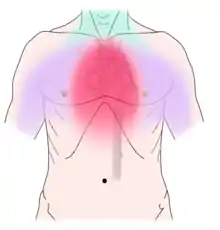

Discomfort caused by coronary artery disease can radiate to the neck, lower jaw and teeth

Non-dental causes of toothache are much less common as compared with dental causes. In a toothache of neurovascular origin, pain is reported in the teeth in conjunction with a migraine. Local and distant structures (such as ear, brain, carotid artery, or heart) can also refer pain to the teeth.[35]:80,81 Other non-dental causes of toothache include myofascial pain (muscle pain) and angina pectoris (which classically refers pain to the lower jaw). Very rarely, toothache can be psychogenic in origin.[10]:57–58